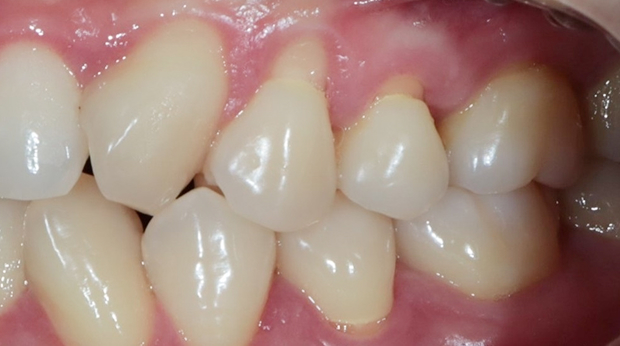

라미네이트